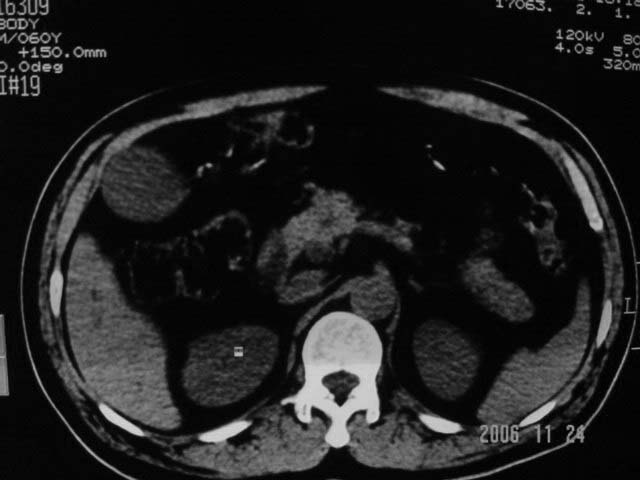

标题: CT5395:男、60岁,皮肤、巩膜黄染伴上腹部疼痛20天 [打印本页]

标题: CT5395:男、60岁,皮肤、巩膜黄染伴上腹部疼痛20天

劳烦各位老师看一下最后一幅箭头指的地方是不是胆总管结石.ct值约63hu.

胆总管内结节状高密度灶,边缘隐约可见低密度环绕,首先考虑结石伴肝内胆管扩张; 2、胆囊增大,胆囊炎

肝内外胆管及胰管均示有扩张,胆囊增大.提示胆总管远端梗阻,可考虑肿瘤或结石或肿瘤伴结石,建议强化扫描

考虑胆总管结石致肝内外胆管扩张,胆囊增大,不像是肿瘤

支持胆总管下段结石并肝内外胆管扩张。